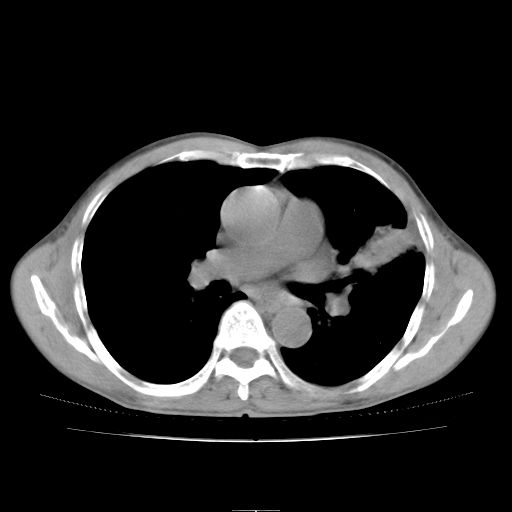

标题: CT25795:感冒后反复咳嗽两月余,痰中带血半月余。X诊断“肺 [打印本页]

标题: CT25795:感冒后反复咳嗽两月余,痰中带血半月余。X诊断“肺

1.双肺肺梗塞(理由:病灶呈三角形,与胸膜相连且局部胸膜肥厚,左心室增大)伴肺感染。

考虑两肺感染性病变,左肺上叶舌段肿瘤性病变待排;建议抗炎治疗后复查。